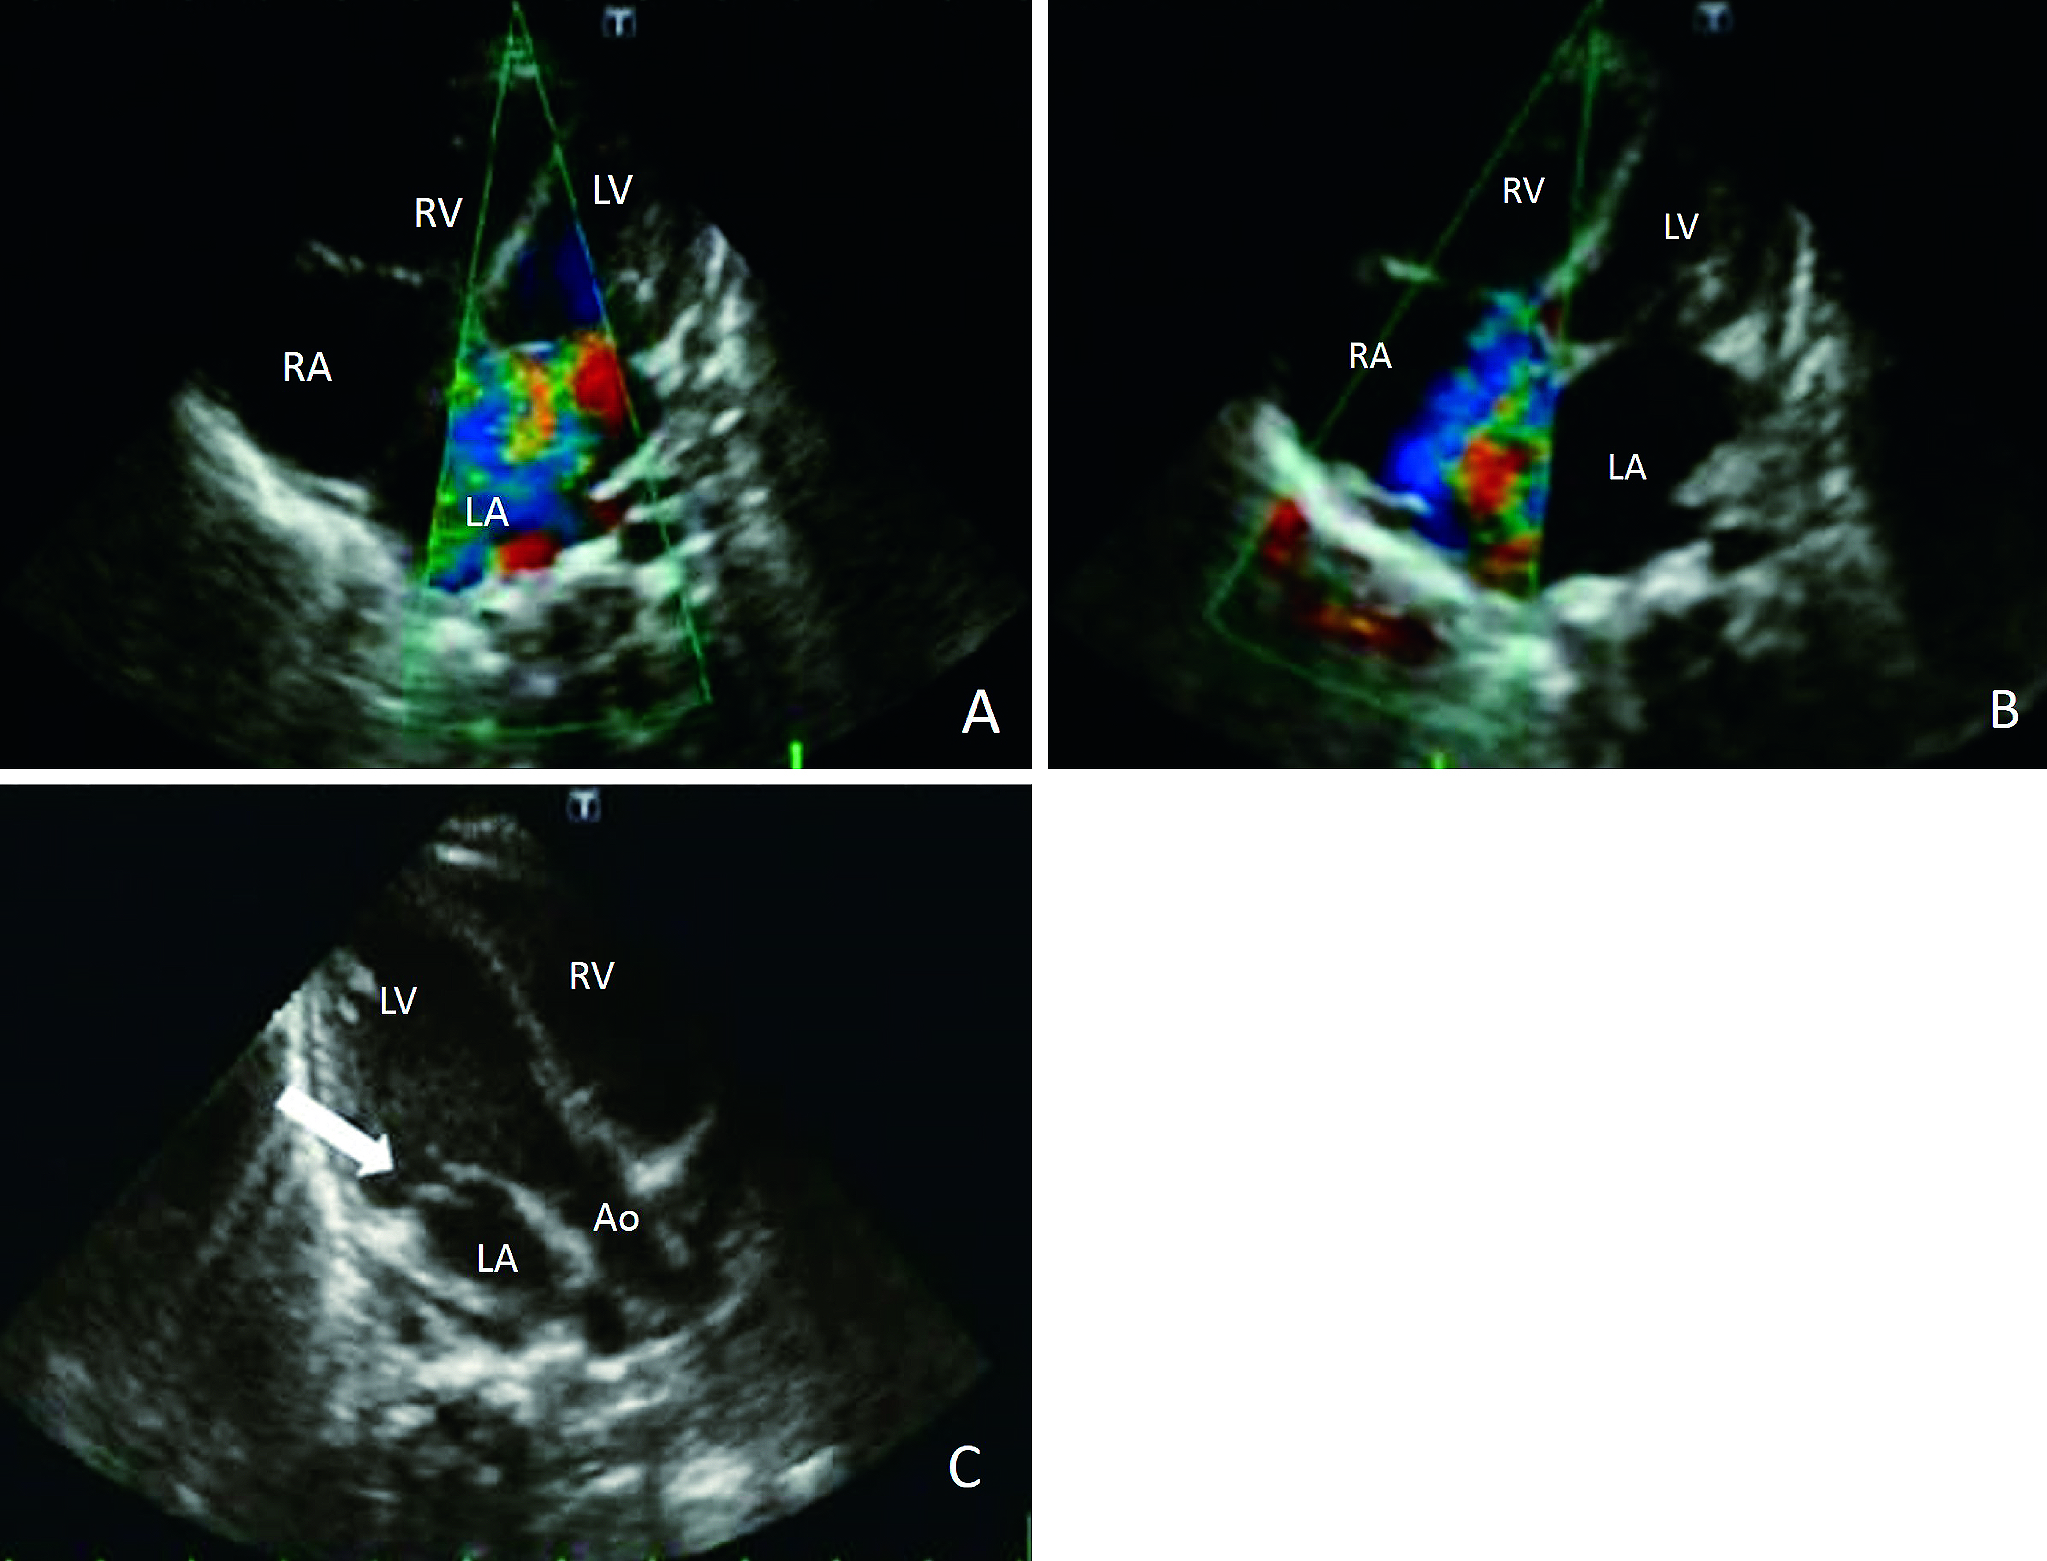

「緊急修復術により救命した乳児突発性憎帽弁腱索断裂例」 - ・第116巻8号 P1223 越智 史博,他